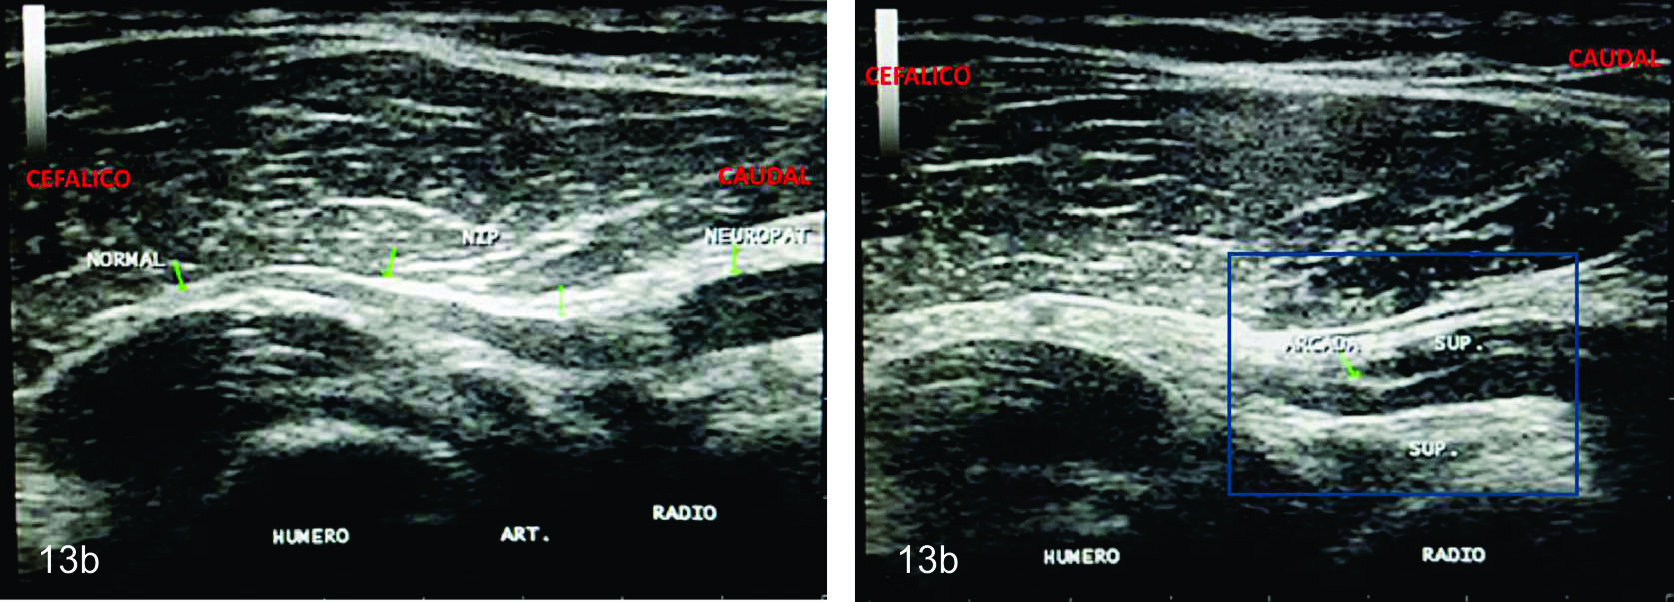

Figura 13 b

Síndrome Interóseo Posterior

Corte ultrasonografico longitudinal del nervio afectado (flechas verdes)- A- Se observa la transición entre el sector cefálico sano del nervio y la zona caudal neuropática. BSe identifica una compresión focal en el nivel de la acrada fibrosa cuando el nervio entra al espacio graso localizado entre ambas cabezas del supinador (Recuadro azul).

Figura 13 a

Corte ultrasonográfico longitudinal del nervio interóseo normal- Se identifica en ambas imágenes el nervio (flechas verdes) como una estructura con forma de cuerda fina, con calibre uniforme cruzando el nivel de la articulación del codo e introduciendose entre ambos vientres del músculo supinador (SUP.)